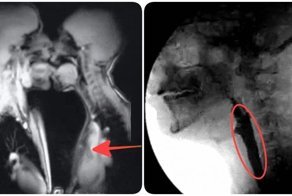

Мать и дитя в МРТ сканере

Ребенок в утробе